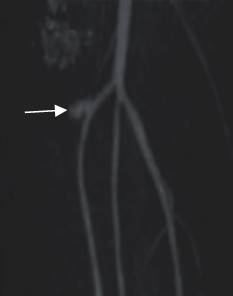

Fig 142 G. Seudoaneurisma.

AngioTAC reconstrucción coronal. Imagen sacular que se dirige hacia la parte medial de la pierna y corresponde a seudoaneurisma de la tibia anterior.